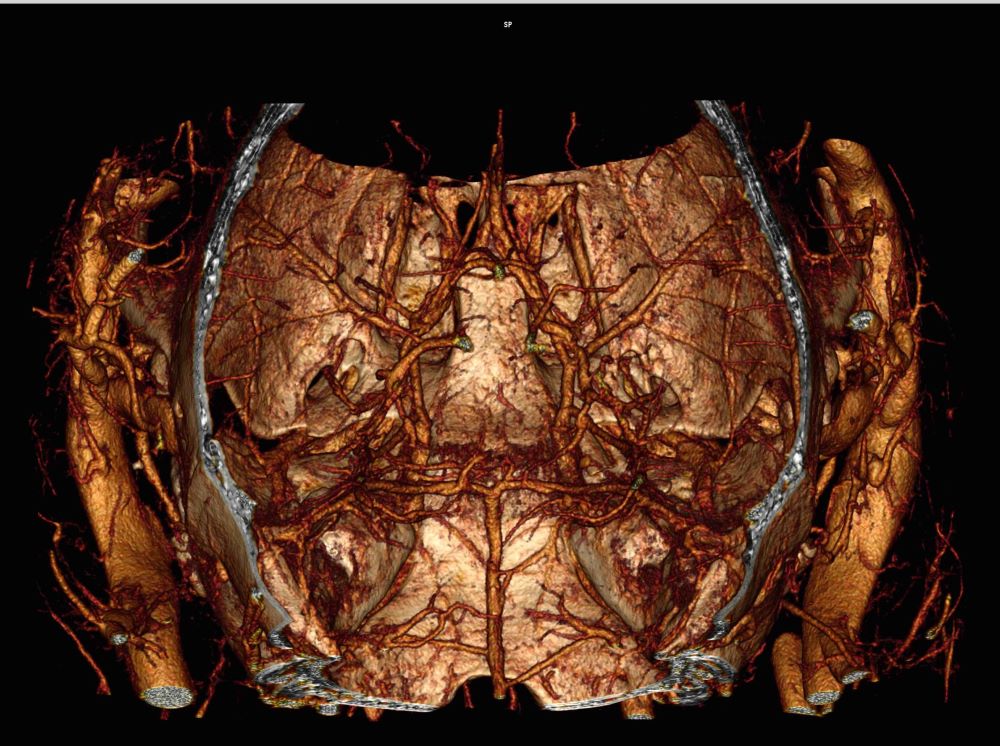

In vivo imaging of mouse cerebral arteries using blood pool contrast agent (Photo: Marrelli Lab)